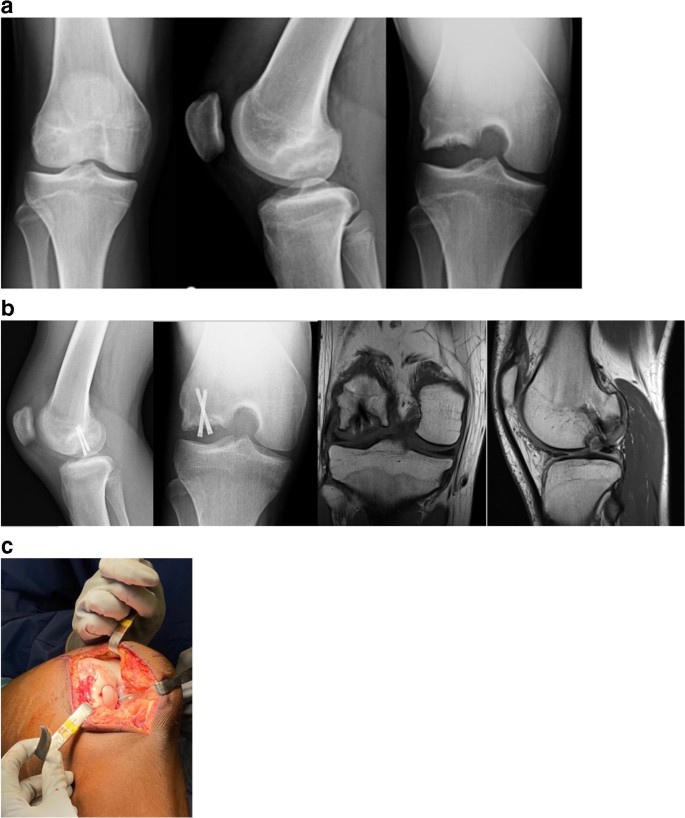

Get Ocd Bone US. Bones offer bearings for all ability levels through a variety of styles including bones swiss ceramics bones bearings has been the manufacturer & distributor of high performance and competition. Osteochondral defects (ocd) or lesions (ocl) are focal areas of damage with articular cartilage damage and injury of the adjacent subchondral bone plate and subchondral cancellous bone.

Plain radiographs are frequently diagnostic altho. From the ocd center of los angeles. Start studying ocd/subchondral bone cysts. Anderson, md, united states carl w.